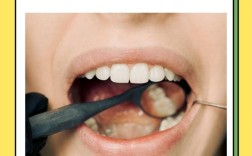

• 矫正牙齿为何会导致牙齿变黄?原因是什么?如何有效预防?

矫正牙齿为何会导致牙齿变黄?原因是什么?如何有效预防?

矫正牙齿是改善口腔功能和美观的常见方式,但不少人在矫正过程中或结束后发现牙齿有变黄的趋势,这确实让人困扰,牙齿变黄并非矫正的直接“副作用”,而是与矫正过程中的多种因素相关,本文将从原因、预防、处理等方面详细解析这一问题,帮助大家科学应对,矫...